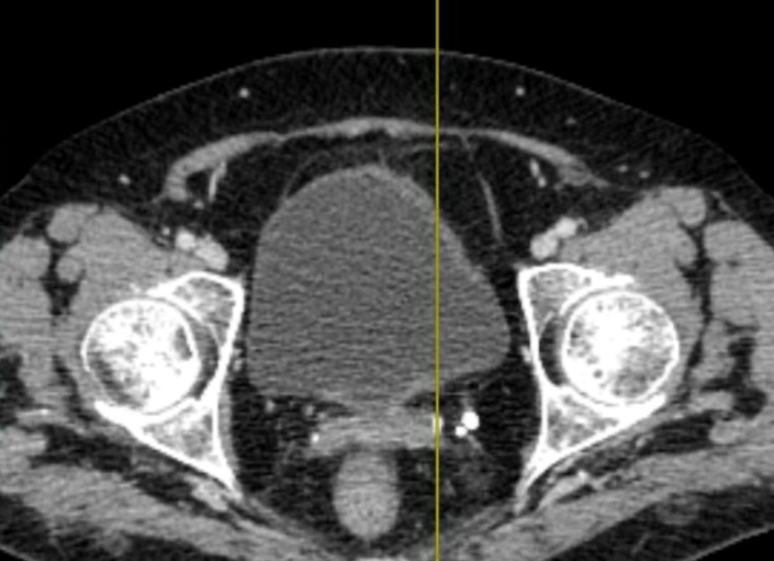

Яичники в постменопаузе постепенно уменьшаются в размерах за счет развития соединительной ткани. Объем яичников в постменопаузальный период составляет в среднем 3 см3, после пяти лет менопаузы — около 2,5 см3, свыше 10 лет — около 1,5 см3 (объем яичников у женщин репродуктивного возраста равен 8,2 см3). Следует подчеркнуть, что выявление у женщин в постменопаузе яичников объемом более 5 см3 является признаком патологии. Разница в объеме правого и левого яичника не должна превышать 1,5 см3. Во время УЗИ необходимо обращать внимание на асимметричное увеличение одного из яичников более чем в два раза, так как в постменопаузе это является одним из признаков малигнизации. В связи с постепенным угасанием гормональной функции яичников наличие единичных маленьких фолликулов в течение первых пяти лет менопаузы не должно расцениваться как патологический процесс. После пяти лет менопаузы фолликулы не выявляются, а их персистенция должна вызывать определенную настороженность.

При трансвагинальном исследовании частота визуализации уменьшенных яичников может достигать 80–90%, а если это же исследование проводить при частично наполненном мочевом пузыре, то точность выявления яичников возрастает до 93,5%. Актуальность вопроса о выявлении яичников при УЗИ определяется тем, что у женщин старше 40 лет возрастает частота возникновения рака яичников.